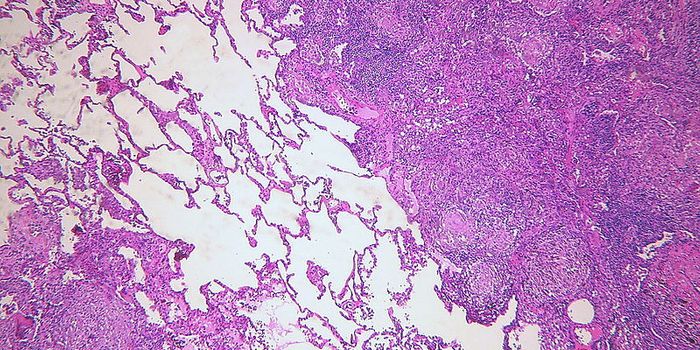

FEB 09, 2024CancerHistopathology describes the process of examining pieces of tissue using a microscope. Light microscopic (LM) exam ...